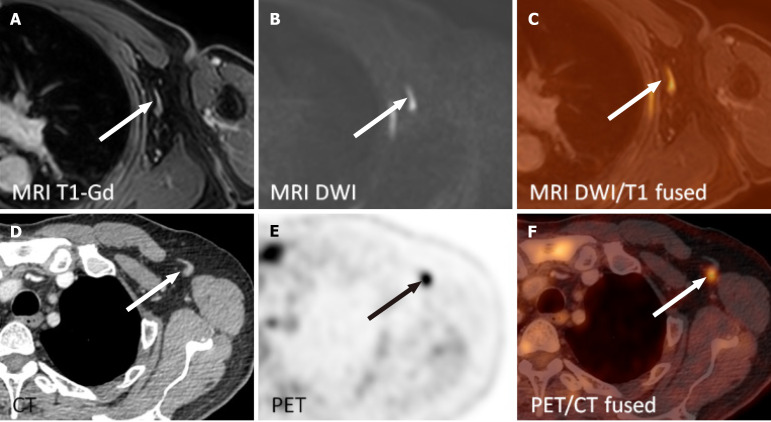

Methods: In this single-center prospective study, adult patients newly diagnosed with systemic DLBCL underwent wbMRI on a 3T scanner [diffusion weighted images with background suppression (DWIBS), T2, short tau inversion recovery (STIR), contrast-enhanced T1] and fluorodeoxyglucose (18F-FDG) positron emission tomography/computed tomography (PET/CT) (reference standard). The involvement of 12 nodal regions and extranodal sites was evaluated on wbMRI and PET/CT. The utility of wbMRI sequences was rated on a five-point scale (0 = not useful, 4 = very useful). Patients received a questionnaire regarding wbMRI.

Results: Of 60 eligible patients, 14 (23%) were enrolled and completed the study. The sensitivity of wbMRI in the nodal involvement (182 nodal sites) was 0.84, with 0.99 specificity, positive predictive value of 0.96, negative predictive value of 0.97, and 0.97 accuracy. PET/CT and wbMRI were concordant both in extranodal involvement (13 instances) and staging (κ = 1.0). The mean scores of the utility of MRI sequences were 3.71 ± 0.73 for DWIBS, 2.64 ± 0.84 for T1, 2.14 ± 0.77 for STIR, and 1.29 ± 0.73 for T2 (P < 0.0001). Patients were mostly concerned about the enclosed environment and duration of the MRI examination (27% of patients).

Conclusion: The wbMRI exhibited excellent sensitivity and specificity in staging DLBCL. DWIBS and contrast-enhanced T1 were rated as the most useful sequences. Patients were less willing to undergo wbMRI as a second examination parallel to PET/CT, especially owing to the long duration and the enclosed environment.